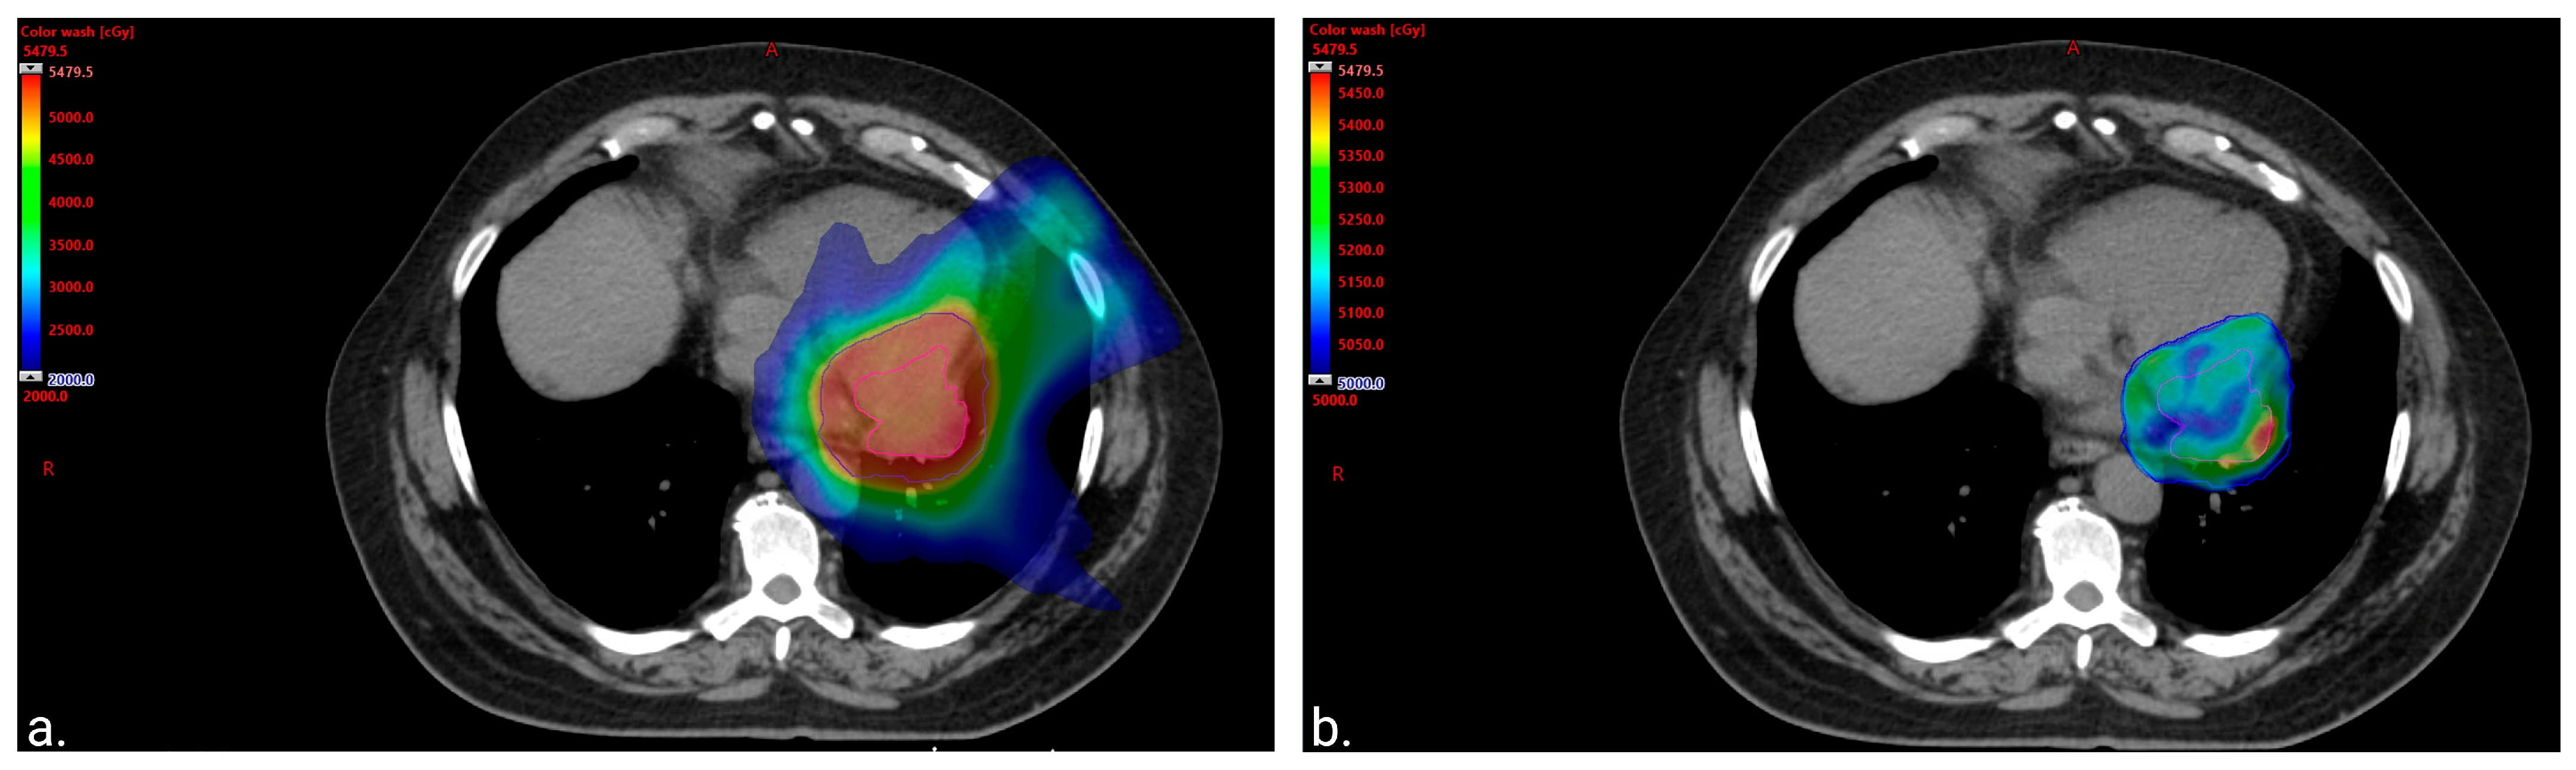

2. Case Report